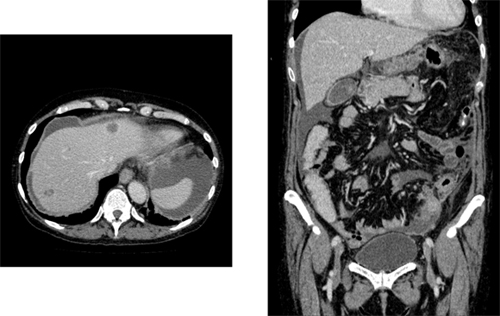

医用画像に興味があっても周りに協働できる医師が見つからない事が多いとおもいますが、現在では匿名化された画像を入手することはそれほど難しくはありません。例えば、日本医用画像工学会では、CAD(Computer-Aided Diagnosis、コンピュータ支援診断)コンテストを毎年開催しており、参加者に実験用CT画像を安価に配布しています(図4)。

図4 公開データベースの例

- 注:門脈相画像:造影剤を注入後約1分後に撮影されるCT画像。肝臓には動脈、静脈という血液循環に加え、腸などで吸収された栄養分を肝臓に運ぶ門脈という血管系があります。